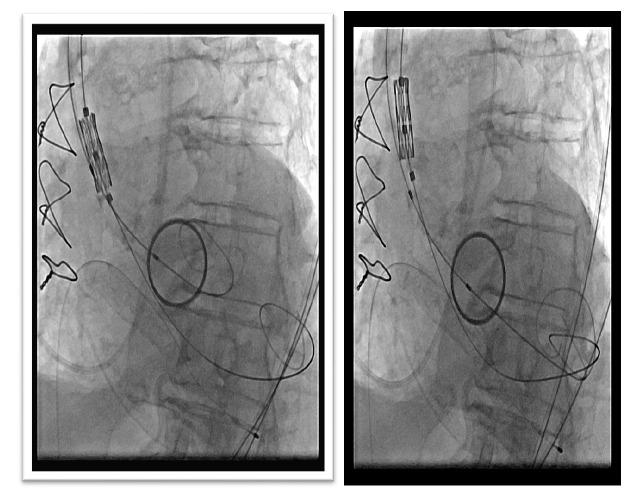

We present a case of an 82-year-old patient in whom the prosthesis was displaced during implantation and later expanded in the descending aorta with a new prosthesis implanted in the aortic valve position.

我们报告一例 82 岁患者,其人工瓣膜在植入过程中发生移位,随后在降主动脉扩张,并在主动脉瓣位置植入了新的人工瓣膜。